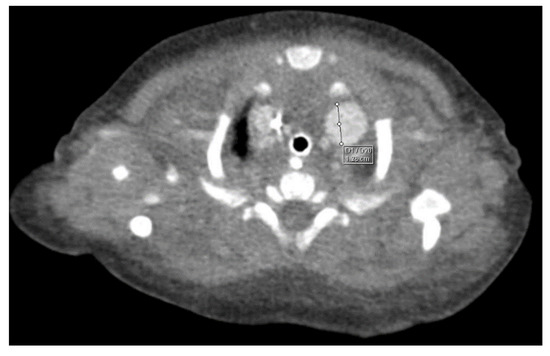

Through thoracic CT, we found SVC with a diameter of 15 mm (Figure 1), a venous collector with a 12 mm in diameter connected to the SVC and identified at the level of a plane passing through the middle of the left superior pulmonary lobe (Figure 2). The venous structure continues superiorly with the left brachiocephalic venous trunk, which was dilated up to 12 mm (Figure 3) and inferiorly with a left pulmonary vein. The pulmonary trunk appeared shorter, with a diameter of 6 mm, right pulmonary artery = 5.4 mm and left pulmonary artery = 5.6 mm (Figure 4 and Figure 5). We have identified traits of pulmonary consolidation (Figure 6).

Figure 4.

Right pulmonary artery.

Figure 5.

Left pulmonary artery.